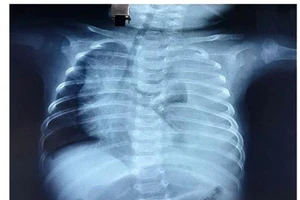

Bé 3 tháng bị rò nửa lít dịch đục như sữa vào phổi mỗi ngày

Cứu trẻ sinh non tràn dịch màng phổi